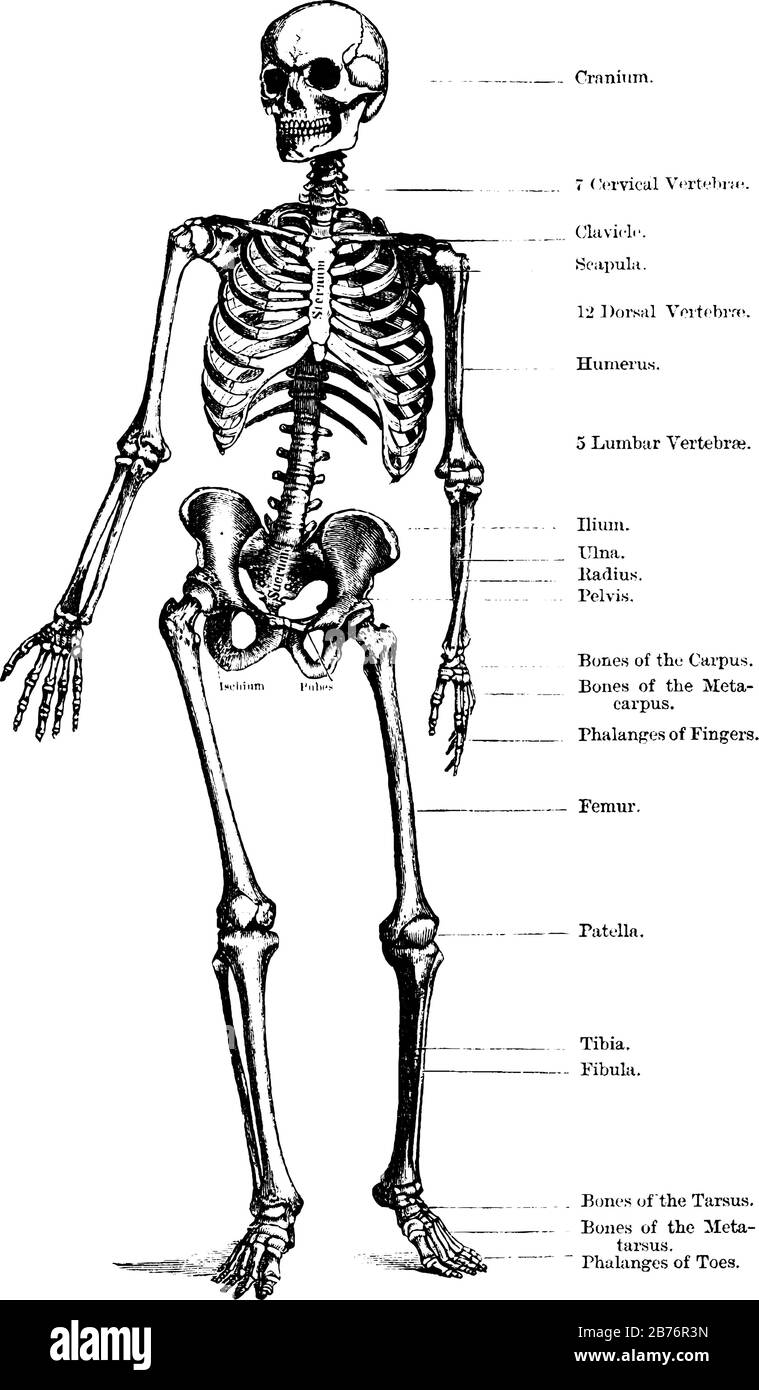

A diagram in which complete structure of human skeleton which is defined clearly, vintage line drawing or engraving illustration. Stock Vectorhttps://www.alamy.com/image-license-details/?v=1https://www.alamy.com/a-diagram-in-which-complete-structure-of-human-skeleton-which-is-defined-clearly-vintage-line-drawing-or-engraving-illustration-image367223577.html

A diagram in which complete structure of human skeleton which is defined clearly, vintage line drawing or engraving illustration. Stock Vectorhttps://www.alamy.com/image-license-details/?v=1https://www.alamy.com/a-diagram-in-which-complete-structure-of-human-skeleton-which-is-defined-clearly-vintage-line-drawing-or-engraving-illustration-image367223577.htmlRF2C9CDBN–A diagram in which complete structure of human skeleton which is defined clearly, vintage line drawing or engraving illustration.

Human skeleton standing upright, vintage line drawing or engraving illustration. Stock Vectorhttps://www.alamy.com/image-license-details/?v=1https://www.alamy.com/human-skeleton-standing-upright-vintage-line-drawing-or-engraving-illustration-image348659801.html

Human skeleton standing upright, vintage line drawing or engraving illustration. Stock Vectorhttps://www.alamy.com/image-license-details/?v=1https://www.alamy.com/human-skeleton-standing-upright-vintage-line-drawing-or-engraving-illustration-image348659801.htmlRF2B76R3N–Human skeleton standing upright, vintage line drawing or engraving illustration.